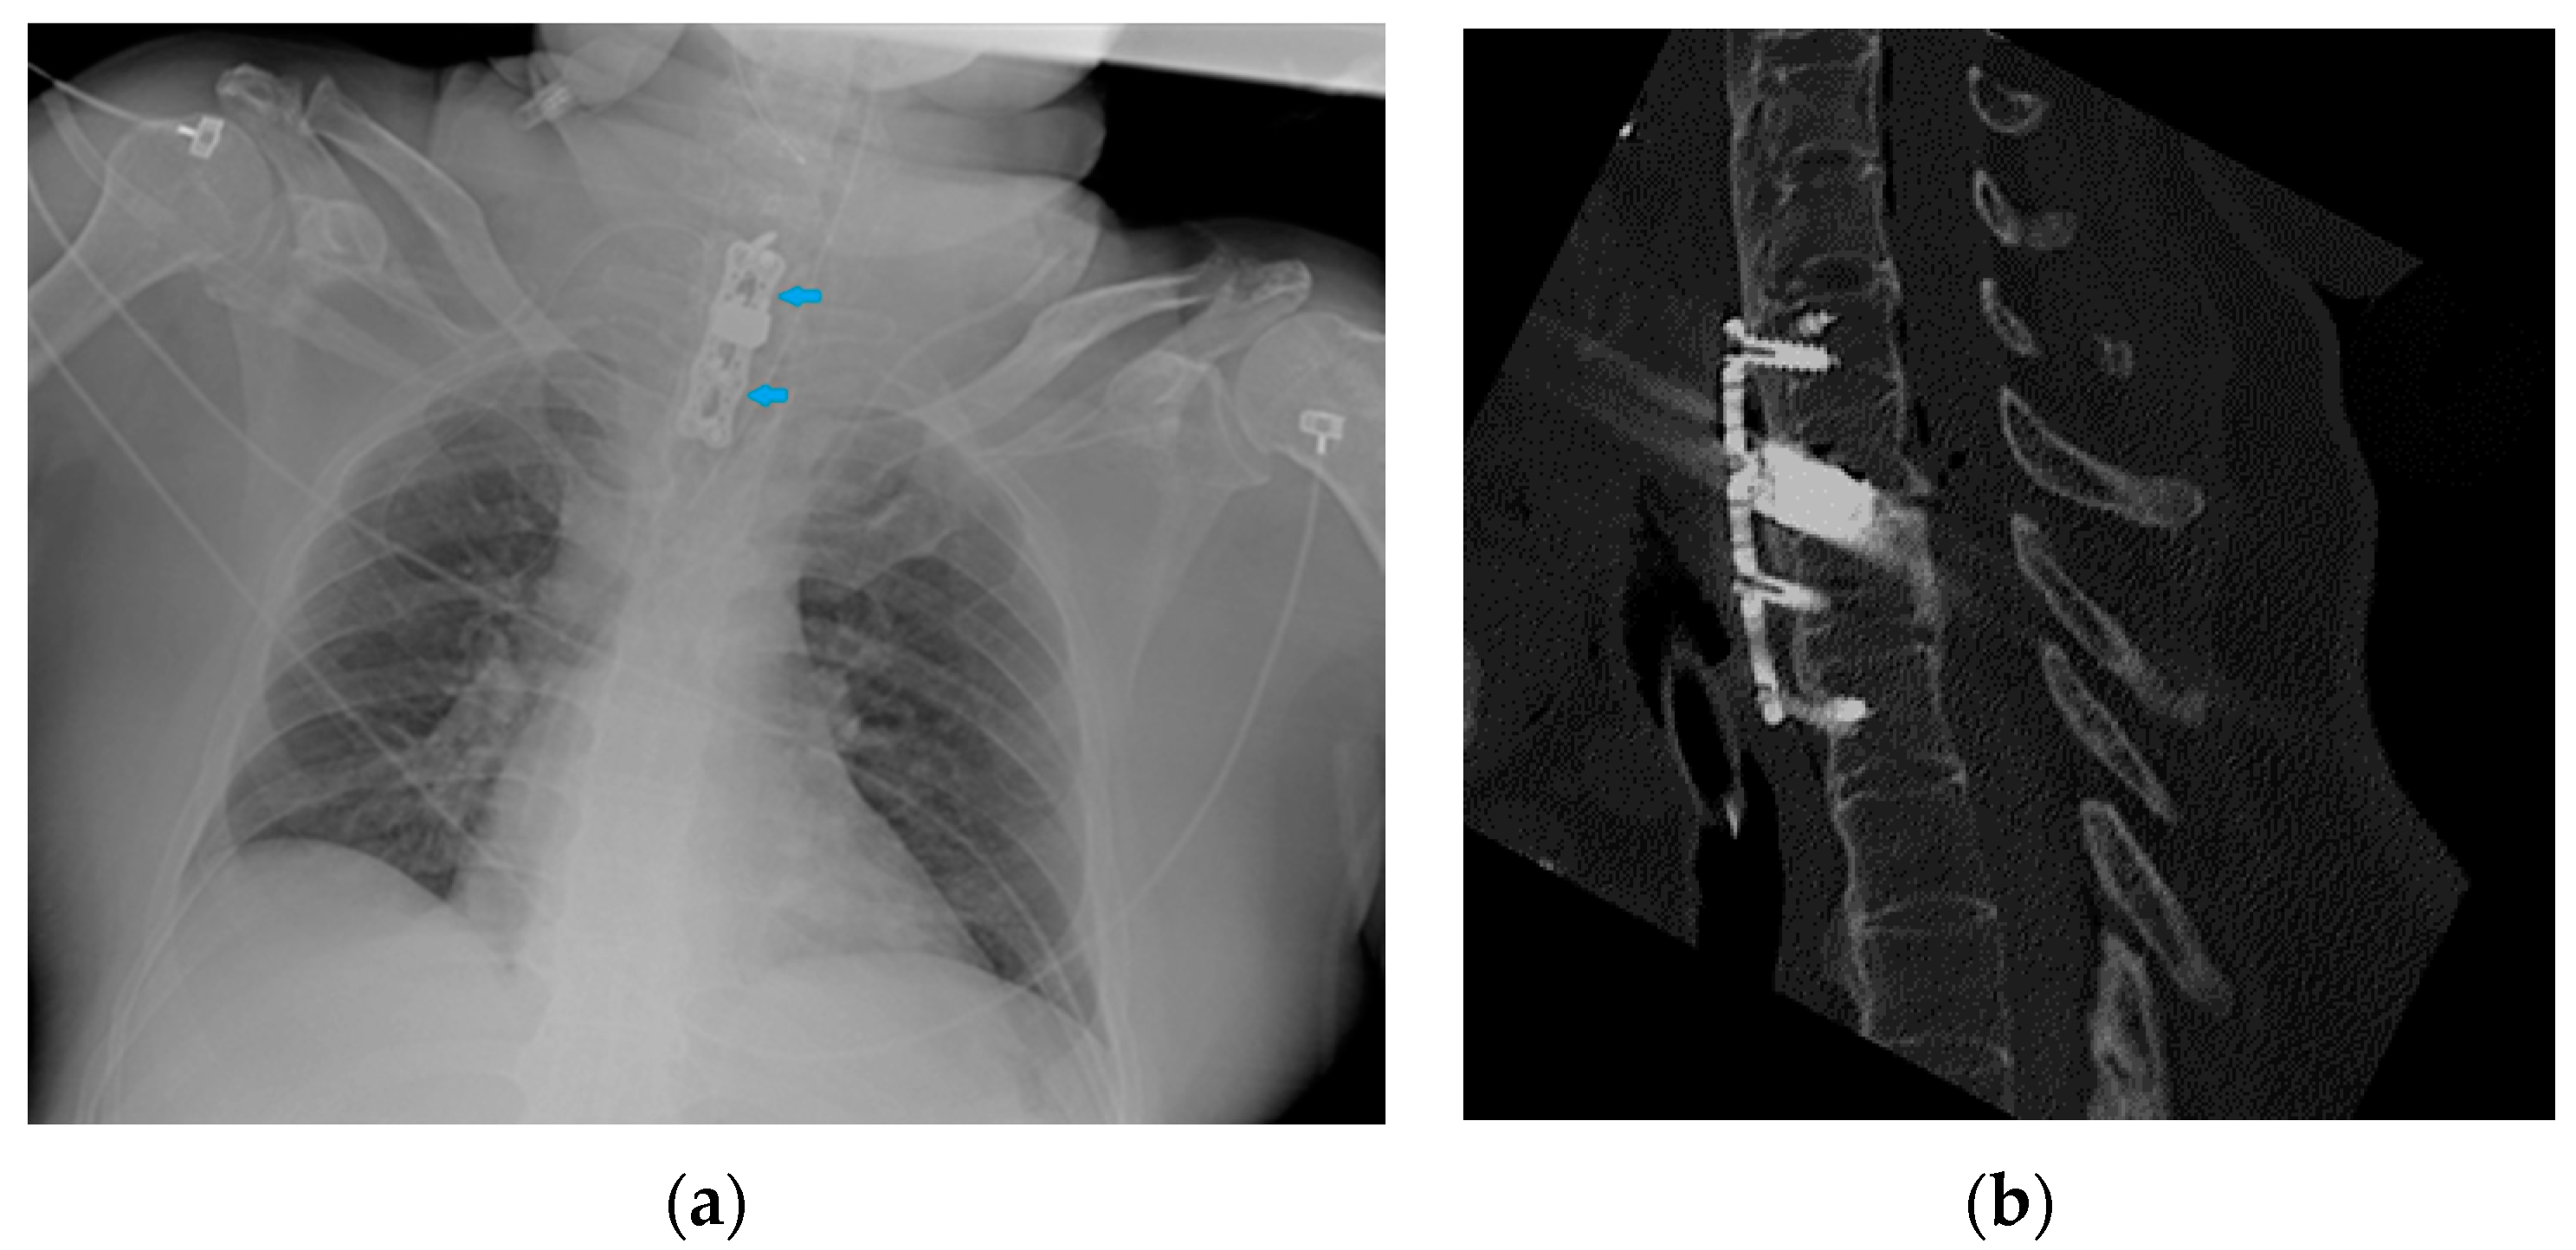

Figure 35.

Image of an anterior spine stabilizer (blue arrows) on CXR (a) and the corresponding image on the CT scan (b).